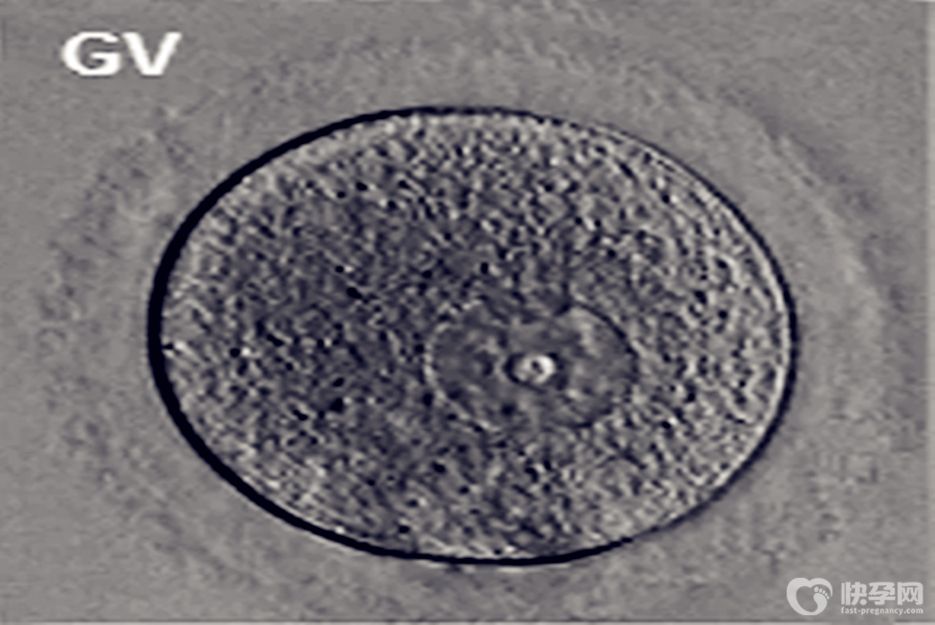

根据卵母细胞的成熟度,即是否开始减数分裂排出第一极体,分为GV,MI,M2三种:

GV卵:GV期的卵母细胞没有恢复减数分裂,将颗粒膜细胞去掉后可以看到明显的核。自然排卵状态下月经第八天卵子即开始长成到GV期。GV卵在正常试管婴儿培养中不能使用。